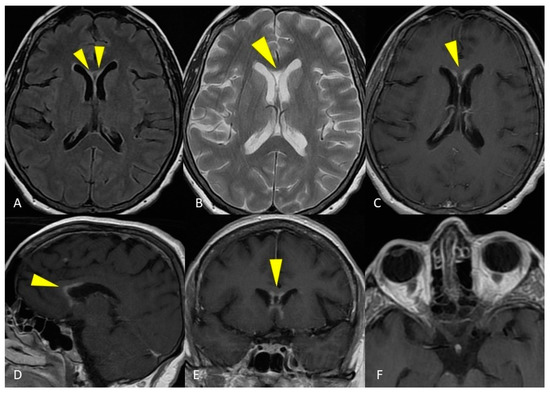

2.1. Case Presentation 1

2.2. Case Presentation 2

3.2. Acute Disseminated Encephalomyelitis—ADEM

3.6. CLIPPERS